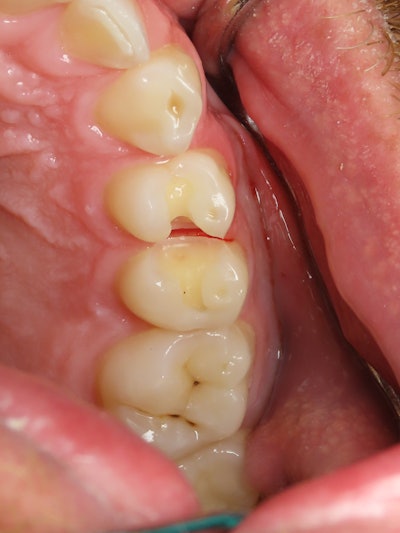

A patient presented for class II restorations due to primary decay on the interproximal surfaces of teeth #12 and #13 (Figure 1 and 2). Clinically the tooth was cold-tested and confirmed a normal response to cold stimulus.

Figure 2: Pre-operative intraoral photo.

Figure 3: Unfinished preparation photo showing decay into the dentin.

Figure 4: Final preparations before the restorations.